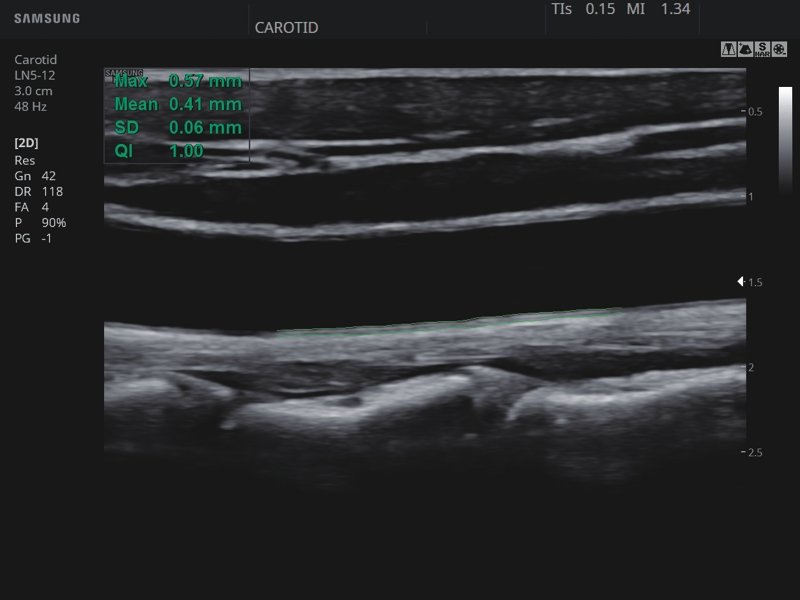

[EN] Эхограмма №822: Общая сонная артерия (ОСА) - автоматическое вычисление комплекса интима-медиа (Intima Media Thickness).

Изображение получено с помощью УЗ сканера HS30 (есть в продаже).